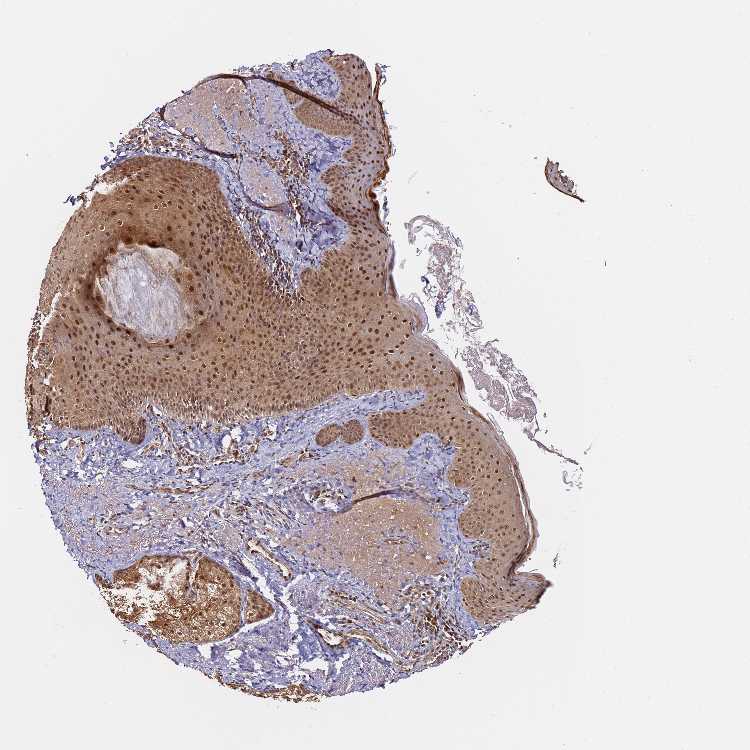

SKIN 2 - Antibody stainingi

Antibody staining in the annotated cell types in the current human tissue is reported as not detected, low, medium, or high, based on conventional immunohistochemistry profiling in selected tissues. This score is based on the combination of the staining intensity and fraction of stained cells.

Each image is clickable and will lead to virtual microscopy that enables deeper exploration of all samples and also displays staining intensity scores, fraction scores and subcellular localization as well as patient and tissue information for each sample.

Antibody HPA045780

Epidermal cells Medium